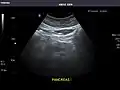

- Pancreas

Pancreas: Visualized portions unremarkable.